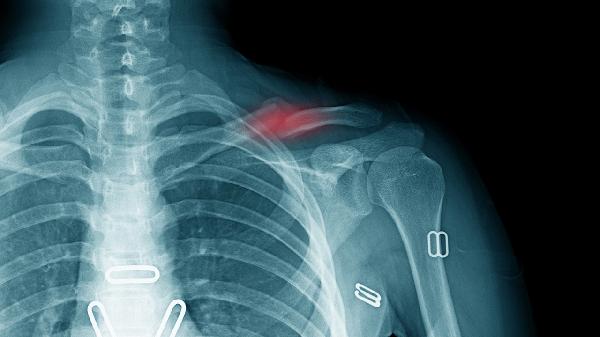

锁骨骨折或锐器伤可能直接损伤动脉血管壁。表现为局部血肿形成伴远端缺血。紧急处理需手术修复血管裂口,术后使用注射用头孢呋辛钠预防感染,联合迈之灵片减轻组织水肿。